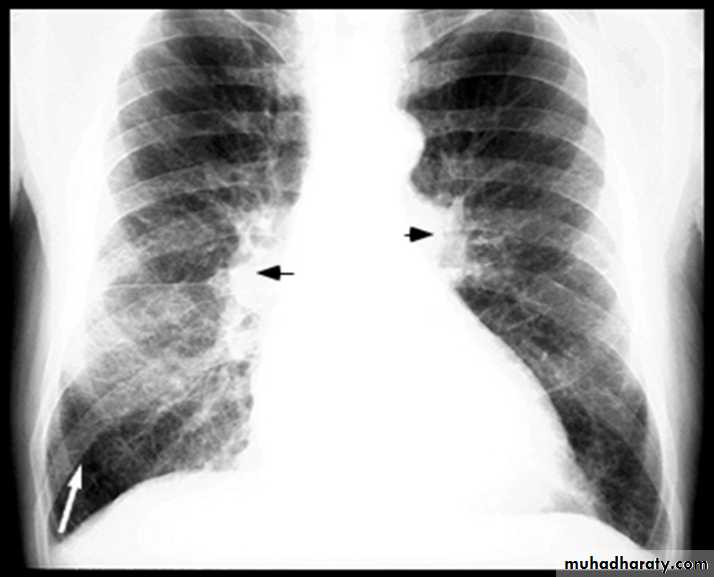

BNP brain natriuretic pepetideChest X-ray in Heart Failure

Kerley B-lines

Pleural effusions

Pulmonary Edema due to Heart Failure

Kerley B lines